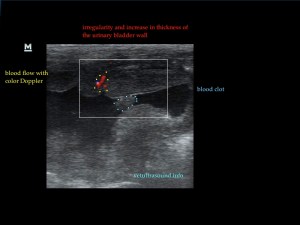

Η πάχυνση του τοιχώματος και η δοκίδωση του βλεννογόνου είναι εμφανής σε όλες τις εικόνες. Πολλές φορές οι λαγόνιοι λεμφαδένες μπορεί να είναι ήπια διογκωμένοι και να έχουν αντιδραστική ηχομορφολογία. Ο έλεγχος με έγχρωμο Doppler του τοιχώματος της άδειας κύστης μπορεί να μας δείξει ροή αίματος στα αγγεία της κύστης. Αντίθετα, είναι πιθανό, όσο η κύστη γεμίζει με ούρο η ροή αίματος να μην είναι ορατή με το Doppler. Αυτό συμβαίνει συχνά στη χρόνια βακτηριακή κυστίτιδα λόγω της ίνωσης του τοιχώματος της ουροδόχου και αυτή είναι μία από τις αιτίες της μη ανταπόκρισης στη θεραπεία. Η συγκεκριμένη παθοφυσιολογία έχει μελετηθεί στον άνθρωπο με την βοήθεια ενδοσκοπικού υπερήχου.

The increase of thickness of the urinary bladder wall and the striation of the mucosa is evident. Inguinal lymphnodes are usually prominent and mildly enlarged. Colour Doppler may reveal the blood flow of the mucosa of the empty urinary bladder, whereas the blood flow in a full bladder appears decreased. This could be because of the fibrosis of the urinary bladder wall and could explain why sometimes chronic conditions like these do not respond well to antibiotics. This pathophysiology has been studied in humans with the use of endoscopic ultrasound.

– Evaluation of blood flow in the mass with colour/power Doppler